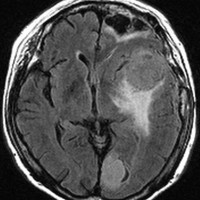

全髄膜の腫瘍化,NF-2

テント下を含めて頭蓋内の全ての髄膜が同時に腫瘍化してきます。この患者さんはNF-2なのですが,NF-2がない患者さんにもmeningiomatosisはあります。脳圧亢進による視神経乳頭萎縮で両側の視力が無くなるというような症状が出ます。これは手術適応がないタイプです。